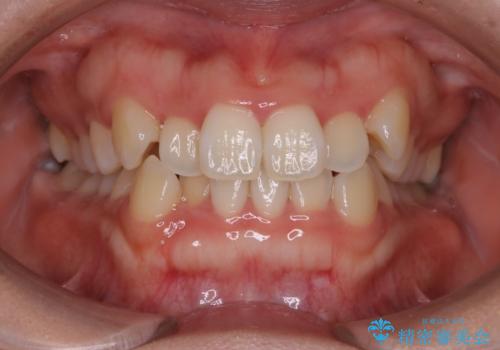

- 上顎の八重歯が気になるとのことで来院されました。

左側のかみ合わせは、歯1本分かみ合わせが前にずれていました。上顎左右の奥歯を2本抜歯しています。

下顎は、歯の側面を少し削ることで歯並びを整えました。

八重歯でがたつきは重度でしたが、きれいな歯並びにすることができました。

がたつきだけでなく、奥歯の噛み合わせのずれの調整もしっかり行いました。